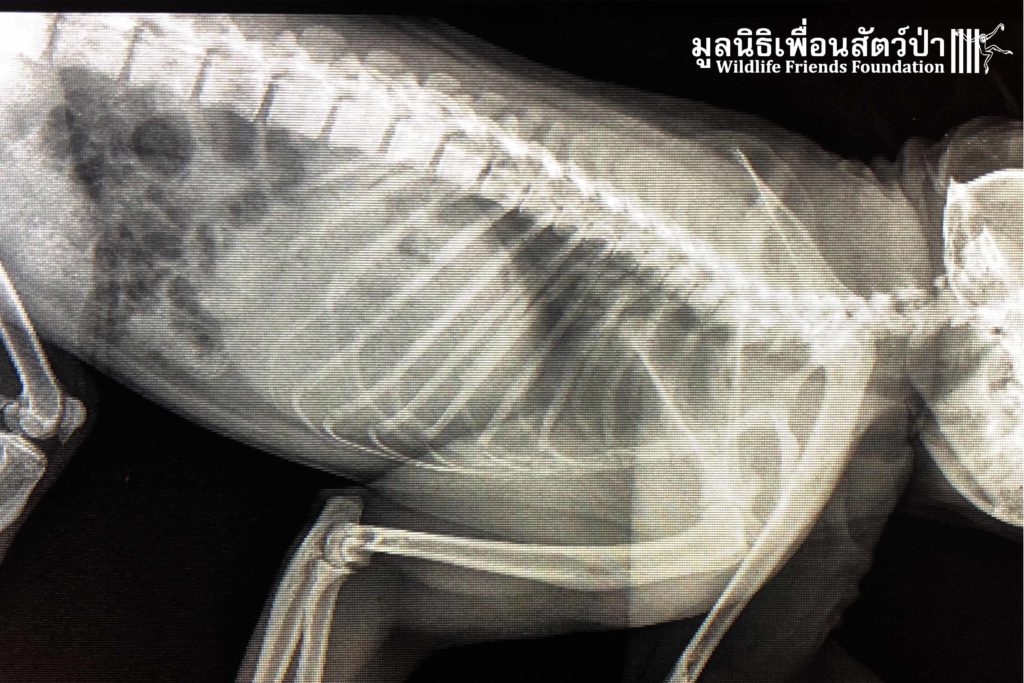

เมื่อทีมกู้ภัยไปถึงพบว่า เจ้าบันไดมีสภาพอ่อนเเอ ไม่เคลื่อนไหวเเต่ไม่มีบาดแผลให้เห็น จึงสันนิษฐานว่ามีกระดูกหักไม่ต่ำกว่า 1 ที่ เเต่เมื่อกลับมา x-ray ที่โรงพยาบาลสัตว์ป่า กลับพบว่าไม่มีร่องรอยหักใดๆ ทั้งสิ้น ทางทีมสัตวเเพทย์จึงคาดการว่าน่าจะได้รับการกระทบกระเทือนทางสมองส่งผลให้ไม่ตอบสนองต่อสิ่งเร้า นอกจากนั้นยังพบกระสุนอีก 2 นัดฝังอยู่บริเวณต้นขา

An x-ray was taken back at WFFT, it was found he has no fractured bones. He may have sustained a large impact to the head, which has caused some brain damage.